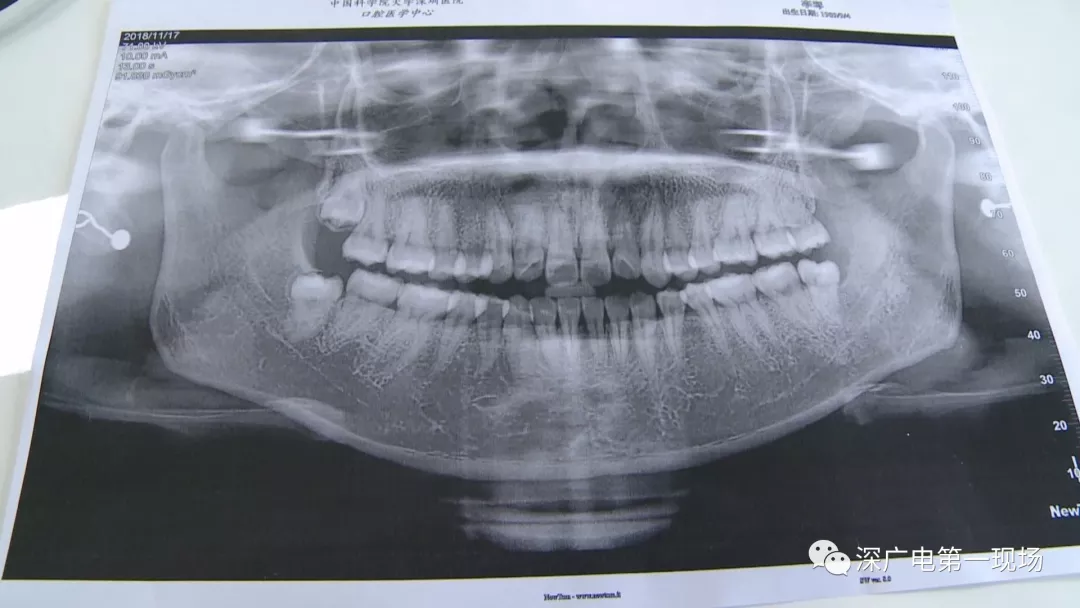

拔一顆智齒一千六?! 深圳這位女士默默的放下了賬單……

中國(guó)科學(xué)院大學(xué)深圳醫(yī)院口腔科主任賈岳介紹,對(duì)于不同患者的牙齒,它的治療方法都不一樣,所以不同牙齒,醫(yī)院收費(fèi)的標(biāo)準(zhǔn)也各不相同。牙齒的治療方案,都是根據(jù)患者牙齒具體情況來(lái)制定,然后再去收費(fèi),同時(shí)也會(huì)參考病人實(shí)際情況來(lái)做不同的治療項(xiàng)目。